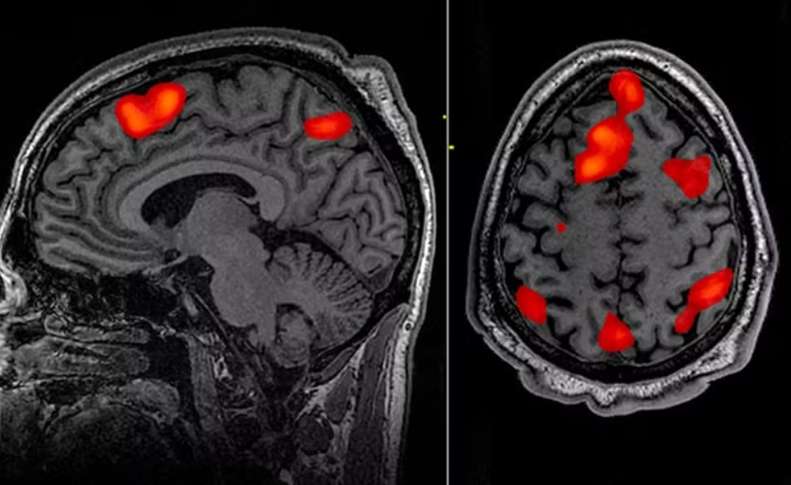

A doença de Huntington, uma condição neurodegenerativa rara, mas cruel e devastadora, foi tratada com sucesso pela primeira vez.

A doença de Huntington é causada por uma mutação no gene da huntingtina, que leva à produção de uma proteína tóxica para os neurônios. A condição provoca perda progressiva de funções motoras, cognitivas e comportamentais, resultando em dependência e morte, geralmente em até 20 anos após o início dos sintomas.